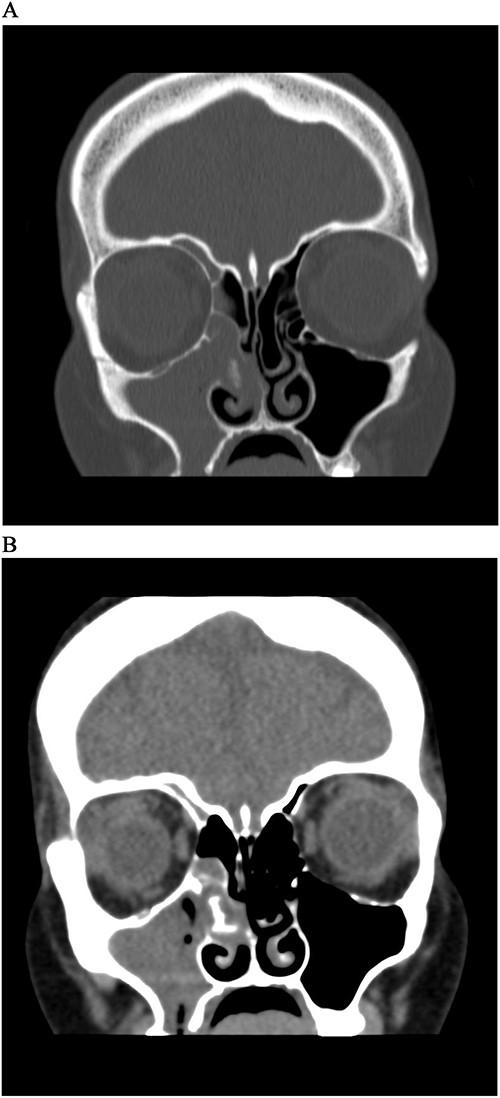

A 41-year-old woman presented to the ENT clinic in January 2020 with right clear to yellowish rhinorrhea. The nasal discharge started 2 months after her cesarean section delivery. On physical examination, nose vestibulitis was noted for that she was treated with antibiotics (Augmentin) for 1 week that significantly improved her symptoms. However, the patient presented 5 months later with 2 weeks history of brownish-to-greenish nasal discharge, in which she was treated again with Augmentin, along with nasal hypertonic saline and mometasone furate sprays. Rhinosinusitis and CSF rhinorrhea were suspected, and a computed tomography (CT) was done. Upon reviewing the CT, it showed complete opacification of the right maxillary and right ethmoidal sinuses with calcifications in the ethmoidal sinus with right ostiomeatal complex obstruction, and mild mucosal thickening at the right frontal sinus with no significant bone lesion (Fig. 1A). The left side sinuses were unremarkable while there was mild nasal septal deviation to the right. She was booked for functional endoscopic sinus surgery (FESS) + septo-turbinoplasty (STP), however, it was postponed due to COVID lock down. The patient was referred to the dental department for root canal therapy.

CT Sinus, bone window (A) and soft tissue window (B), coronal cut, shows complete opacification of right maxillary sinus and anterior ethmoidal cells, with a soft tissue mass extending from MM to septum with hyperdensity lesion.